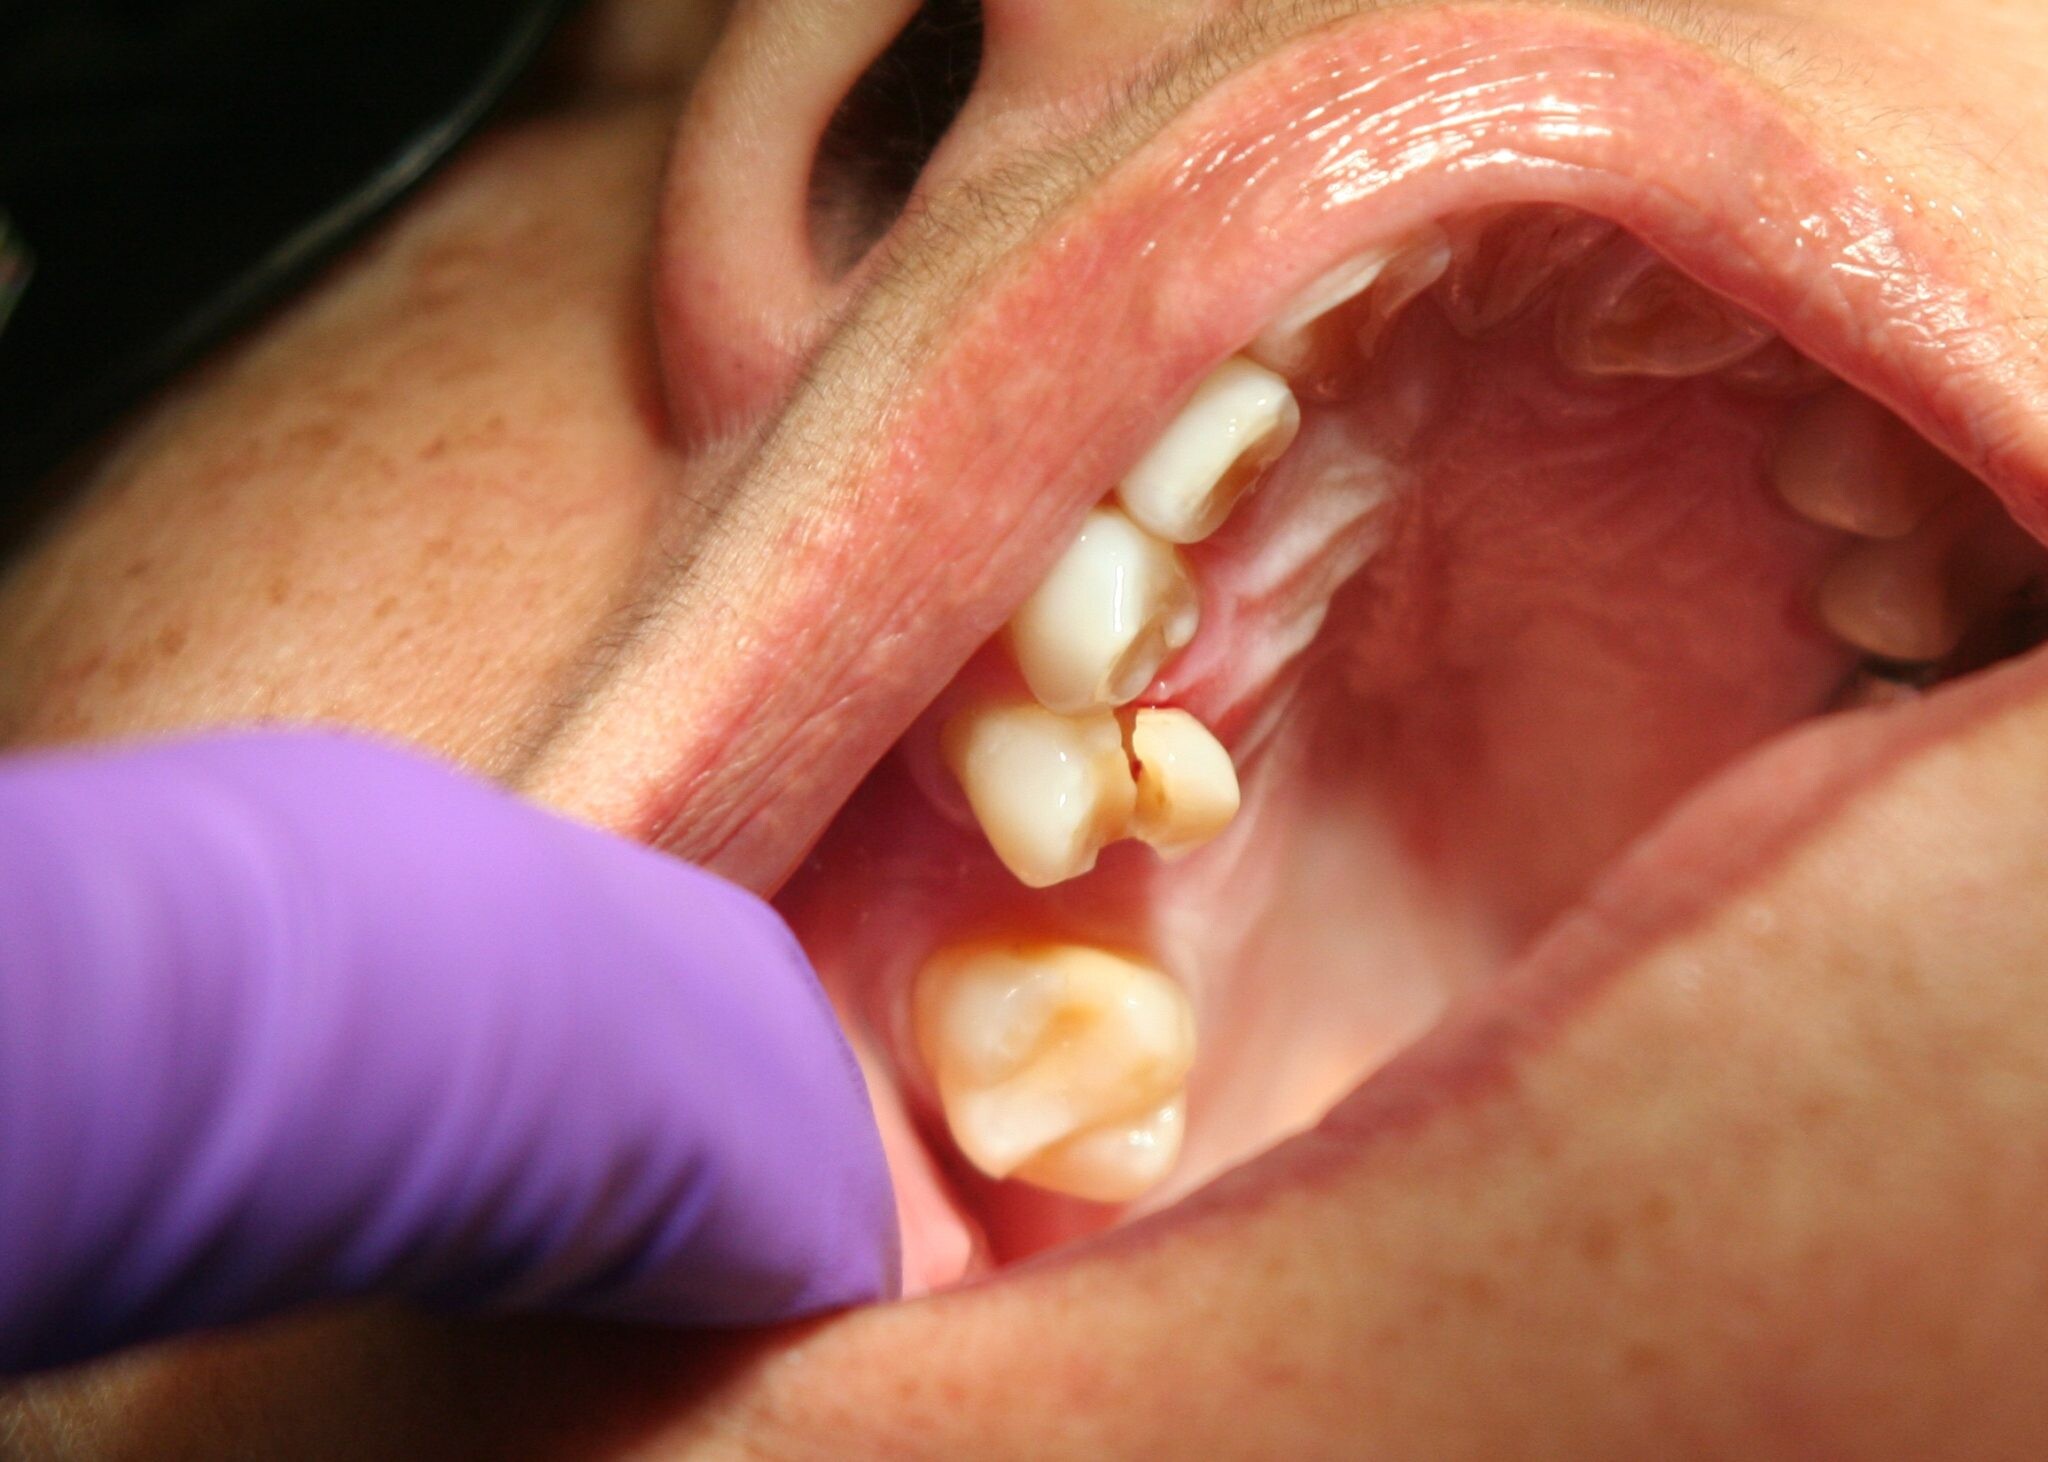

Oral Health Problems

In some cases, jaw pain on one side can indicate underlying oral health problems. Some common issues that cause jaw pain are cavities, an abscessed tooth, gum disease, tooth decay, growth of wisdom teeth, missing or crooked teeth, and clenching or grinding your teeth.